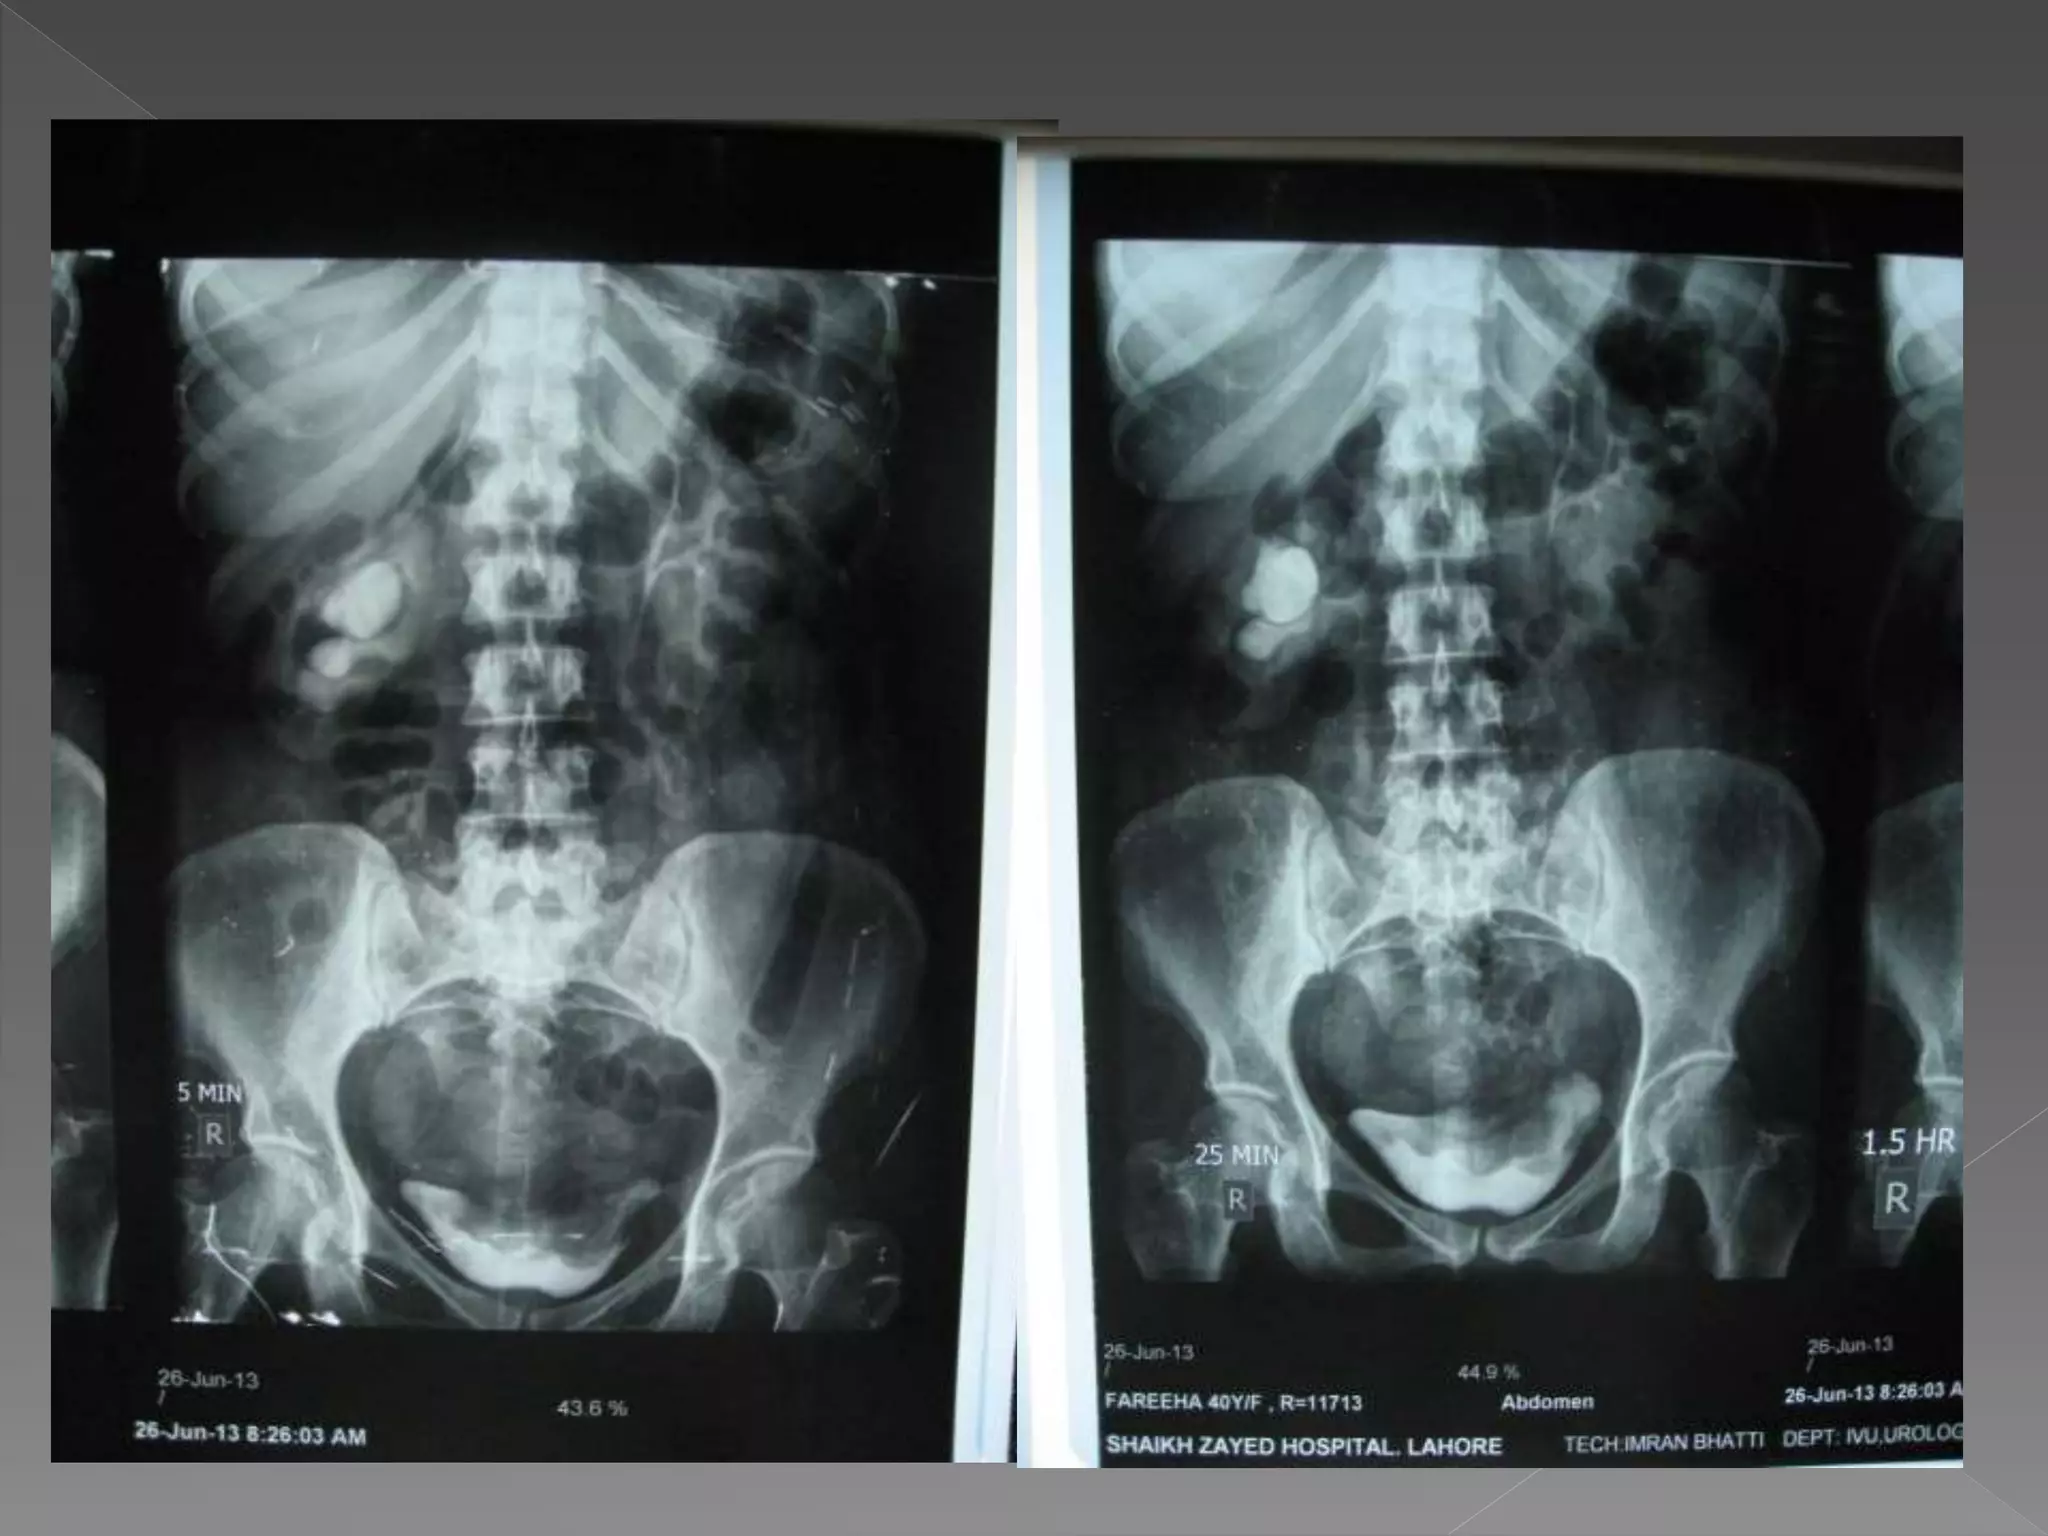

1) Pre contrast

2) 5 mins

3) 25 mins

4) Post void

X ray films 1)Pre contrast 2) 5 mins 3) 25 mins 4) Post void